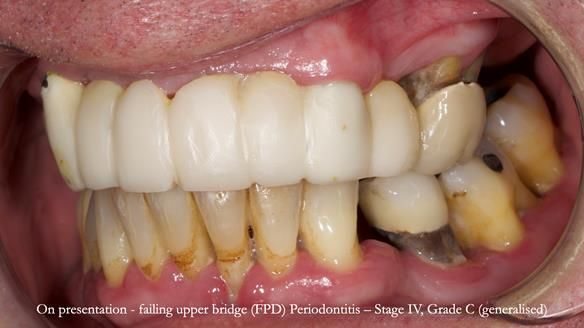

Jeremy’s upper bridge, supported by the canine teeth (13 and 23), was failing both aesthetically and functionally.

- On smiling, the bridge was clearly visible and did not look natural, as the ceramic had been ground back.

- Functionally, the bridge was unstable, due to Periodontitis – Stage IV, Grade C (generalised).

- The upper molars (UR7 and UL7) had also failed and required removal.